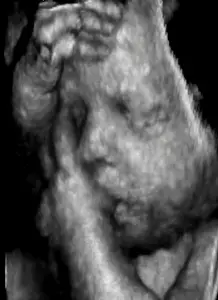

- The ultrasound machine displays the distances and intensities of the echoes on the screen, forming a 2D image like the one shown below.

The ultrasound that we have described so far presents a 2D image, or “slice,” of a 3D object (fetus, organ). Two other types of ultrasound are currently in use, Three Dimensional (3D) ultrasound imaging, and Doppler ultrasound.

In 3D Ultrasound machines, several 2D images are acquired by moving the probes across the body surface or rotating inserted probes. The 2D scans are then combined by specialized computer software to form Three dimensional images.

- visualizing a fetus to assess its development